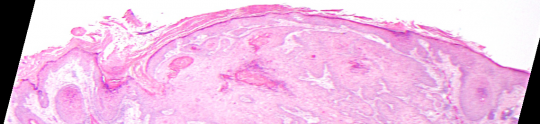

VA9: Left Forearm, Squamous Cell Carcinoma, Invasive

VA9: Left Forearm, Adjacent Normal